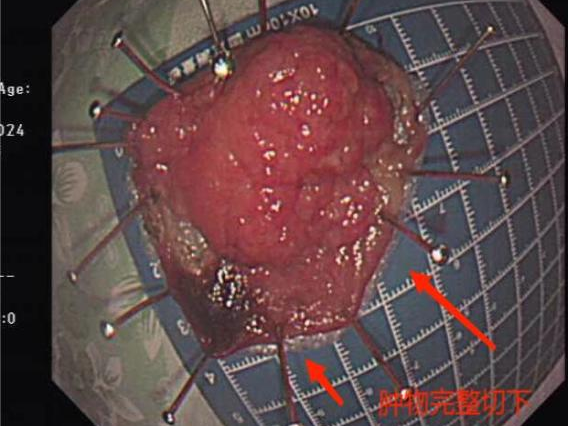

揭XX,女,73岁,因“大便带血20余天,发现大肠多发息肉半个月”入院。入院前门诊肠镜提示大肠多发息肉,病理提示:(直肠)管状绒毛状腺瘤,少许腺体呈高级别上皮内瘤变。入院后次日行经内镜直肠肿物粘膜下剥离术(ESD)。术后病理提示:(直肠)管状绒毛状腺瘤,部分腺体呈高级别上皮内瘤变,局灶癌变(粘膜内癌);手术切缘净。

张XX,女,73岁,因“发现直肠多发肿物、降结肠息肉9天”入院。入院前门诊肠镜提示:1、直肠多发肿物2、降结肠息肉。病理提示:(直肠)管状绒毛状腺瘤,腺体呈低级别上皮内瘤变,建议将整个肿物切除送检进一步明确诊断。入院后次日行经内镜直肠肿物粘膜下剥离术(ESD)。术后病理提示:直肠管状绒毛状腺瘤,部分腺体呈高级别上皮内瘤变,局灶癌变(粘膜内癌);手术切缘净。

以上两名患者的直肠肿物均通过超级微创的消化内镜手术完整切除,体表无切口,肠道无穿孔,腹腔无感染,创伤小,术后恢复快,术后病理提示手术切缘净,达到了与传统外科手术治疗相同的效果,但创伤远小于传统外科手术。其中一例患者的直肠肿物距肛缘仅2cm,消化内科团队通过超级微创的内镜手术,不仅成功完整将肿物切除,还保留了患者的肛门,避免了患者余生要与“屎袋”共度,大大提高了患者的生活质量及生命的尊严,治疗得到患者的肯定和认同,收到患者锦旗致谢。